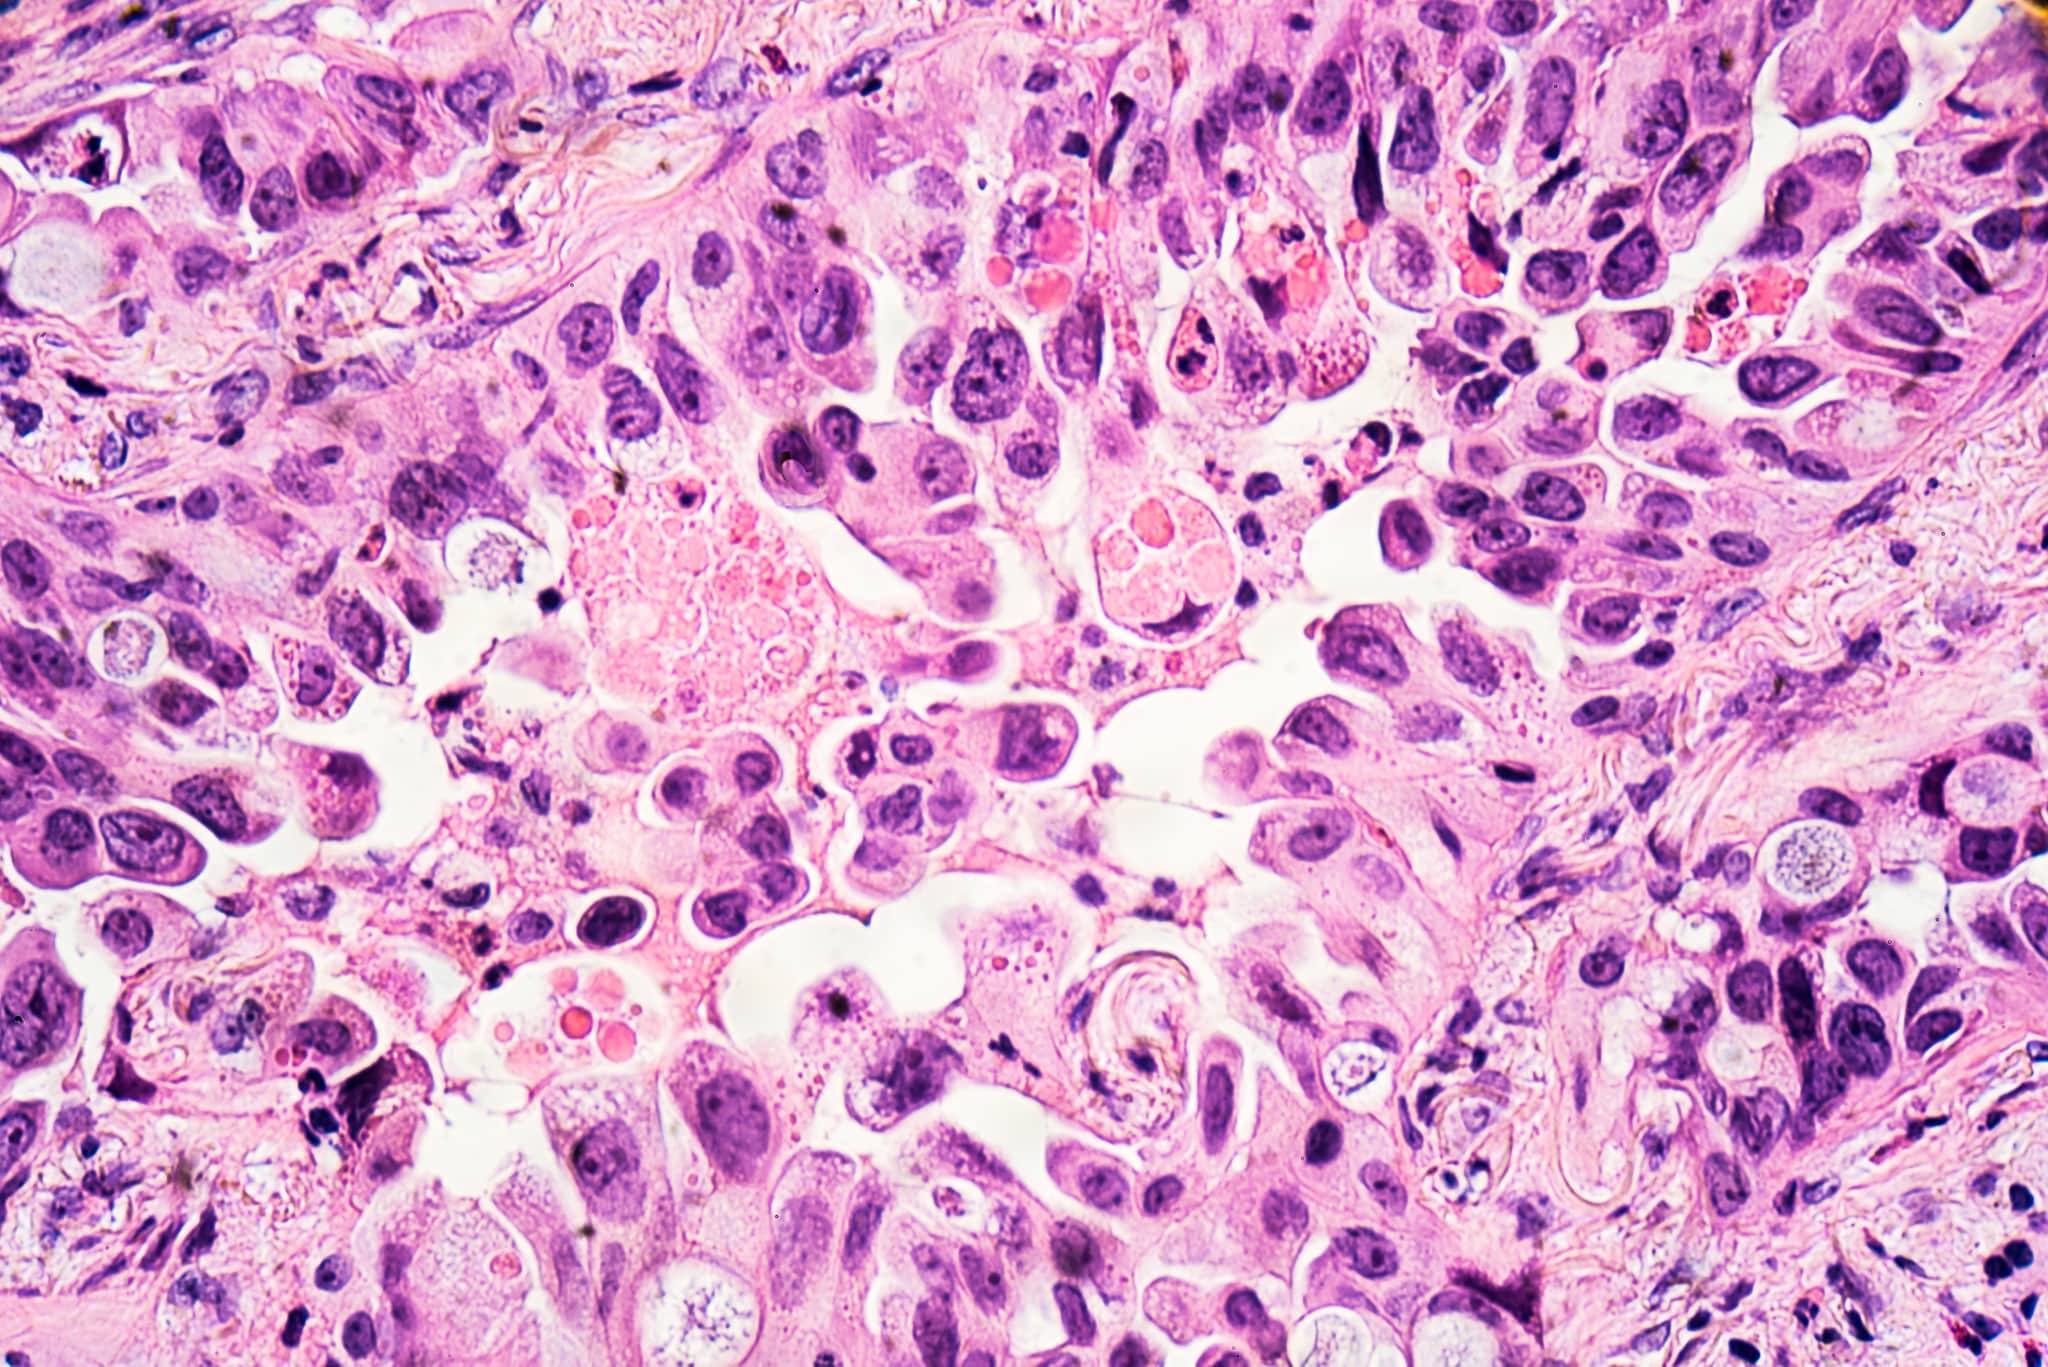

Lung cancer is the third most common cancer in the UK. We played a vital role in reducing the burden of lung cancer through our work to lower smoking rates and protect people from second-hand smoke, but it's still the leading cause of cancer deaths in the UK. Lung cancer survival has lagged behind other cancers, so our scientists are leading the quest for better treatments to bring hope to patients.

From studying the biology of lung cancer cells in the lab to leading clinical trials testing cutting-edge treatments, our researchers are working hard to ensure more people survive lung cancer.